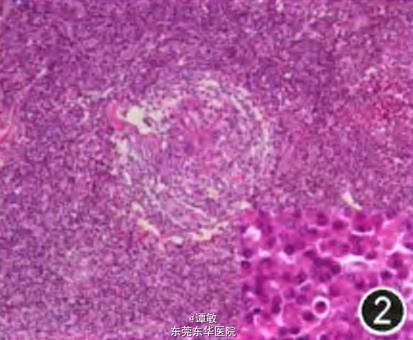

因诊断不明,在全身麻醉下行胸腔镜下心包前肿物切除术,术中发现肿物2块,1块位于右侧心膈脚附近与心包外脂肪融合生长,直径约为5 rm,触之质地较韧。另1块位于左侧心包外脂肪内,大小为4 cm x 6 cm,与左侧心包外脂肪融合。切除组织的病原学检查阴性,病理回报:巨淋巴结增生(Castleman,浆细胞型,图2)。免疫组织化学染色CD138、CD38、浆细胞、CD38及CD31阳性,CD21及CD23部分阳性。